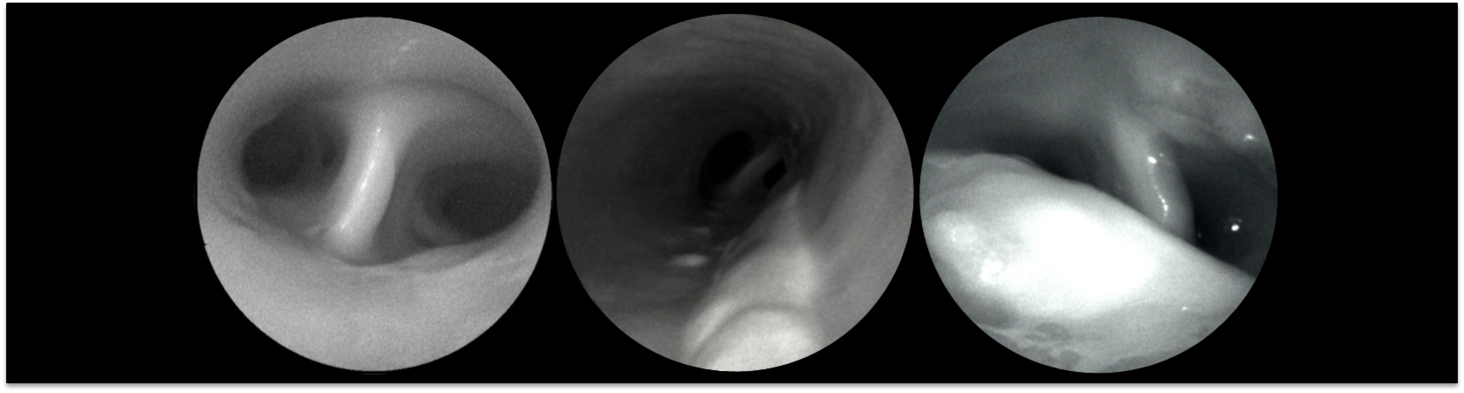

Figure 3 | Scanning

fiber angioscopy of the carotid-artery bifurcation of a donor with a history of

stroke of 'unknown cause' revealed an ulcerated plaque on structural

images (a) with a 'salt-and-pepper pattern' in fluorescence mode (b,c). Pseudocolor map of fluorescent intensity in (b), resulting from exposed

necrotic material to the arterial lumen as showed by histology (c).